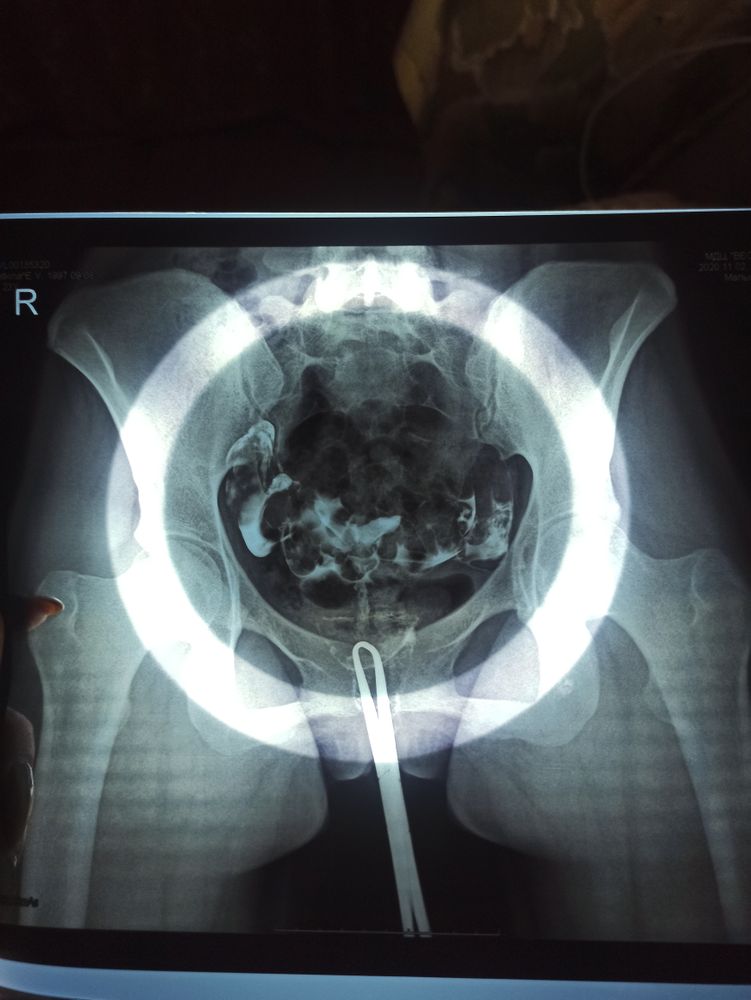

Гистеросальпинография - это проверка проходимости маточных труб путем введения жидкости в матку и снимков ренгтена. Репродуктолог сказал, что данная процедура разрывает спайки если они есть(т.к. жидкость вводиться под давлением), выталкивает жидкость которая нарушает проходимость.

Сама по себе процедура болезненная ( открывают шейку матки, вводят жидкость шприцом😬) длиться 10 минут примерно. Сделали 2 снимка сразу после ввода жидкости и через 5 минут. Они особо ничем не отличаются 🤷

Результаты забрала на следующий день, трубы проходимы.